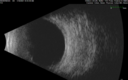

56 year old Asian male - The patient noticed a shadow superiorly about a week ago and then his vision dropped in the right eye. The left eye is OK. Medical Hx: Hypertension, Systemic. Hyperlipidemia. Pre-Diabetes (H1Ac 6.5; not dx yet still monitoring). Surgical Hx: Noncontributory. Systemic Meds: HCTZ. Lisinopril. ATORVASTATIN. Aspirin 81 mg. CYCLOBENZAPRINE HCL. VA OD: HM, OS: 20/40 IOP OD: 11, OS: 13 He ultimately had a vitrectomy in the right eye. The left eye failed to respond to Avastin but did beautifully with PDT. Anterior segment: 1+ NS OU Posterior Pole: OD: Vitreous hemorrhage Right eye – hemorrhagic RD 1/20/21 OD Vitreous heme, Massive Subretinal Hemorrhage (3/4 of retina), Cataract - PPV, PPL, Transscleral Biopsy of SR Heme 1/5/22 OD PPV - Suture Akreos 25.00 Akreos PCIOL Left eye - IPCV Avastin monthly – PED growing despite 7 monthly injections PDT 7/27/21 and 12/7/21 – great response

Massive subretinal hemorrhage right eye - polypoidal choroidal vasculopathy243 viewsPatient had sudden vision loss right eye. Had vitrectomy. The left eye had IPCV not responsive to avastin but he did respond to PDT. See album notes for more detail.00000